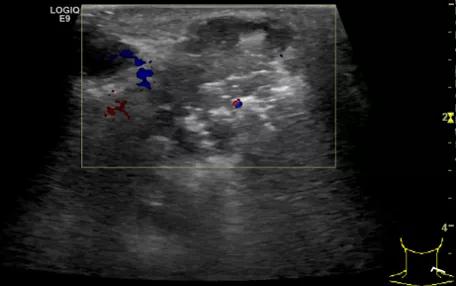

第二例是食管癌患者,术后半年余锁骨上固定淋巴结可触及肿大,疼痛非常明显,系统治疗后无缓解,患者希望通过局部处理缓解症状。造影显示强化信号明显,结节部分区域坏死,故主要针对强化区域从后向前的逐层的消融,皮下进行液体隔离减少烫伤。热消融后影像显示血流增强消失,弹性、硬度增高,一个月后复查显示充盈缺损,完全消融,疗效远超预期。

(病例2图例)